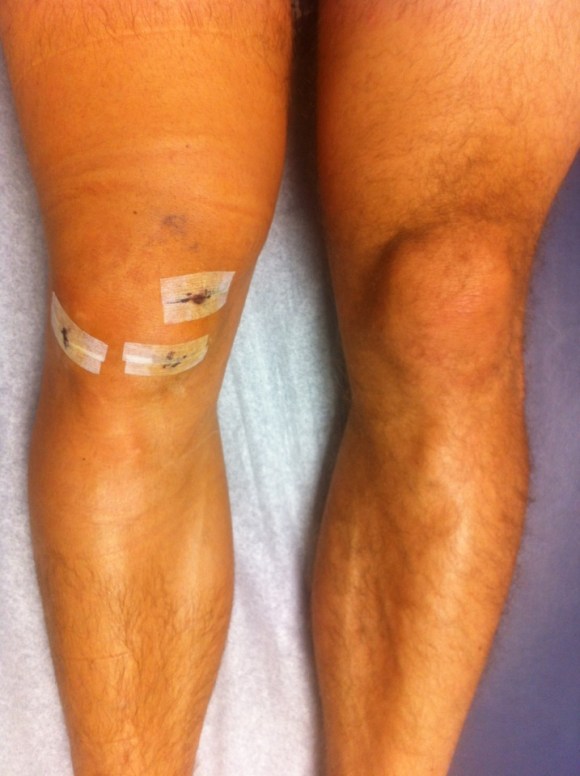

yummy, but no real swelling.

So, you’re wondering, how did the shoulder respond? It basically did not swell-nothing in the hand or arm—compared to the knee where I had swollen foot, toes, and ankle (I iced those too, btw). The incisions on the knee took 2 weeks to fully close on two of the cuts, and one cut today, 4 weeks post op still has a small scab.  The incisions on the shoulder aren’t even noticeable on two of the cuts, and one has a minor scab on the very end of the cut. I keep lying to the physical therapist who asks me if I’m icing, because I’m not. Today I did weight assisted pull-ups at the gym, and that is 12 days post op. This past weekend I had the pleasure of walking around the perform better summit surprising everyone there that I wasn’t limping or in a sling. Hooray for technology, hooray for eating well, and hooray for getting to talk to Gray Cook, Dallas Hartwig, K-Starr, Jon Fass and Doc Cheng regarding the injury and healing.